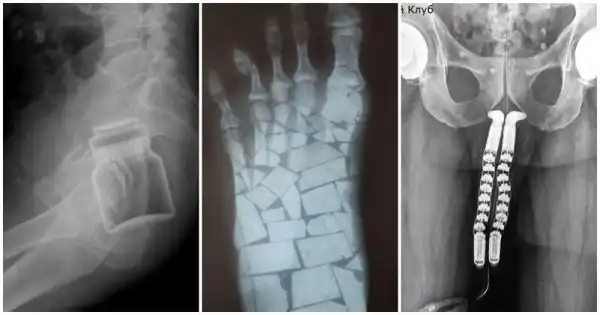

Пациент выслал фото врачу. Тот долго не мог понять, что со стопой

Просто выбирайте нормальный фон!

На фото процесс смены пола: вы видите рентген-снимок пациента на этапе трансплантации полового органа